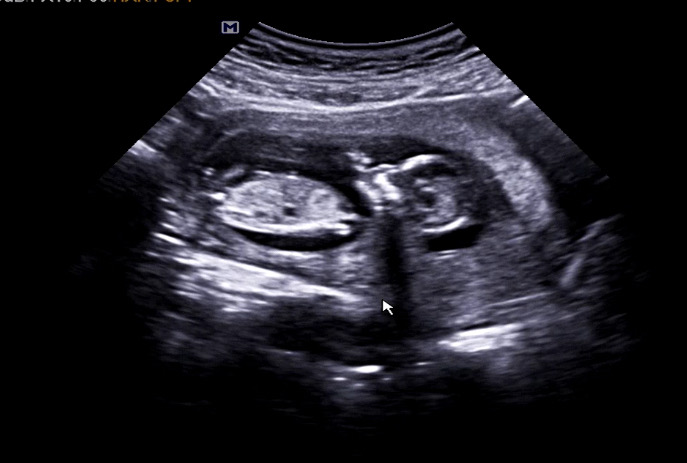

각도법 참견좀 많이 해주세요😭❤️❤️❤️❤️

아들 ? 딸 ? 참견 마니마니 해주세요❤️❤️🙏🏻

잘 보이지 않아서 구분이 안가네요 ㅠㅠ